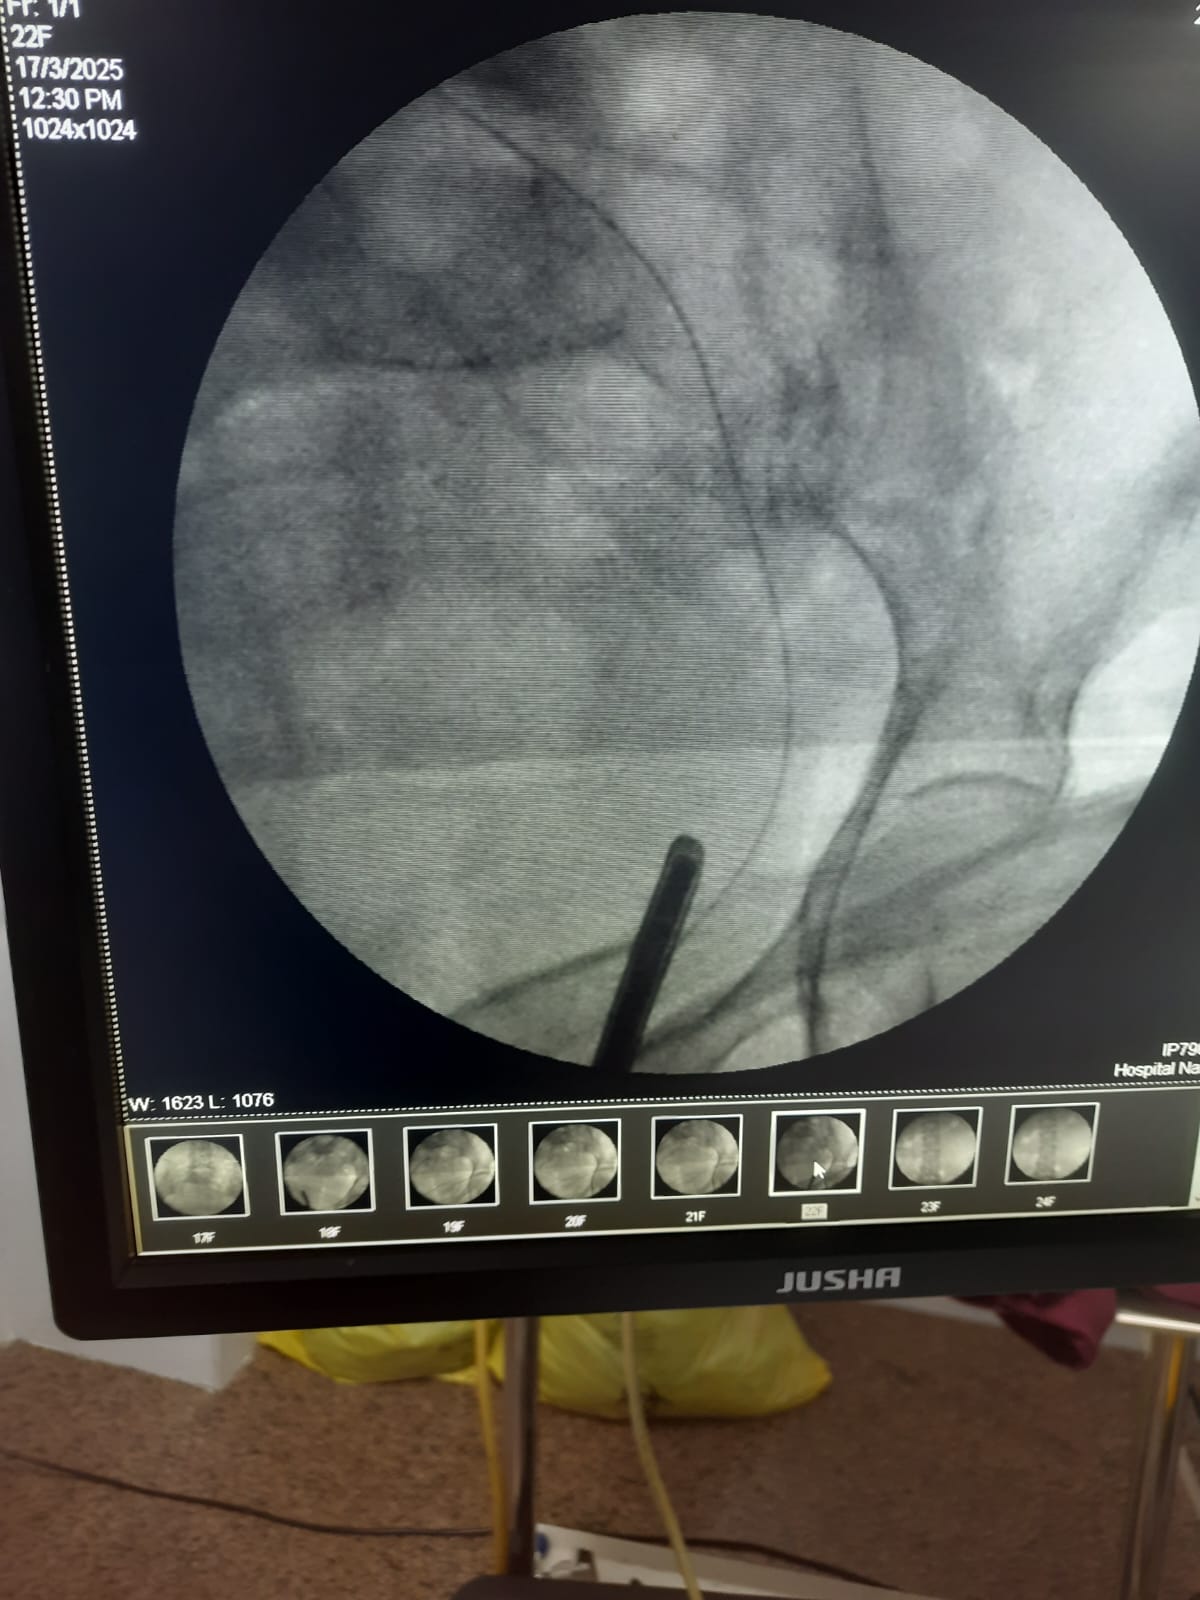

Initial attempts at retrograde left ureteric stenting were hampered by a completely adherent stone, preventing the passage of a standard guide wire. A subsequent thinner, hydrophilic Terumo guide wire was easily negotiated past the obstruction. A diagnostic anomaly was noted when the passage showed an unusual rightward curvature upon successful navigation, leading to suspicion of misplacement.

Following the easy passage of the hydrophilic wire, a 3Fr ureteric stent was passed over it. The stent advanced without resistance, but the proximal pigtail did not coil in the renal pelvis, heightening the suspicion of misplacement. An immediate post-procedure CT scan confirmed the stent's location: the distal end was correctly within the bladder, but the main body and proximal end were located outside the ureter, passing into the Inferior Vena Cava. However, further investigation with MRI of Abdomen revealed that the stent had migrated from the bladder to the left internal iliac vein and reached in the Right Atrium. The patient remained hemodynamically stable. A team meeting was sought, including the opinions of the Cardiologist, Cardiothoracic surgeon, and Urologist, and came to a conclusion that a attempt via endovascular retrieval of the stent. Initial attempts by interventional cardiology via the femoral vein to the Right Atrium failed. Successful retrieval was achieved by an alternative access via the right internal jugular vein, direct entry into the left internal iliac vein. A snare catheter was skillfully deployed to secure the distal end of the DJ stent. The stent was removed successfully without any immediate vascular complication. The patient was monitored in the MICU post-procedure. On the second day post procedure, patient developed mild hematuria and was treated conservatively, and repeat CT KUB with contrast was done, which did not show any remnant fistula.